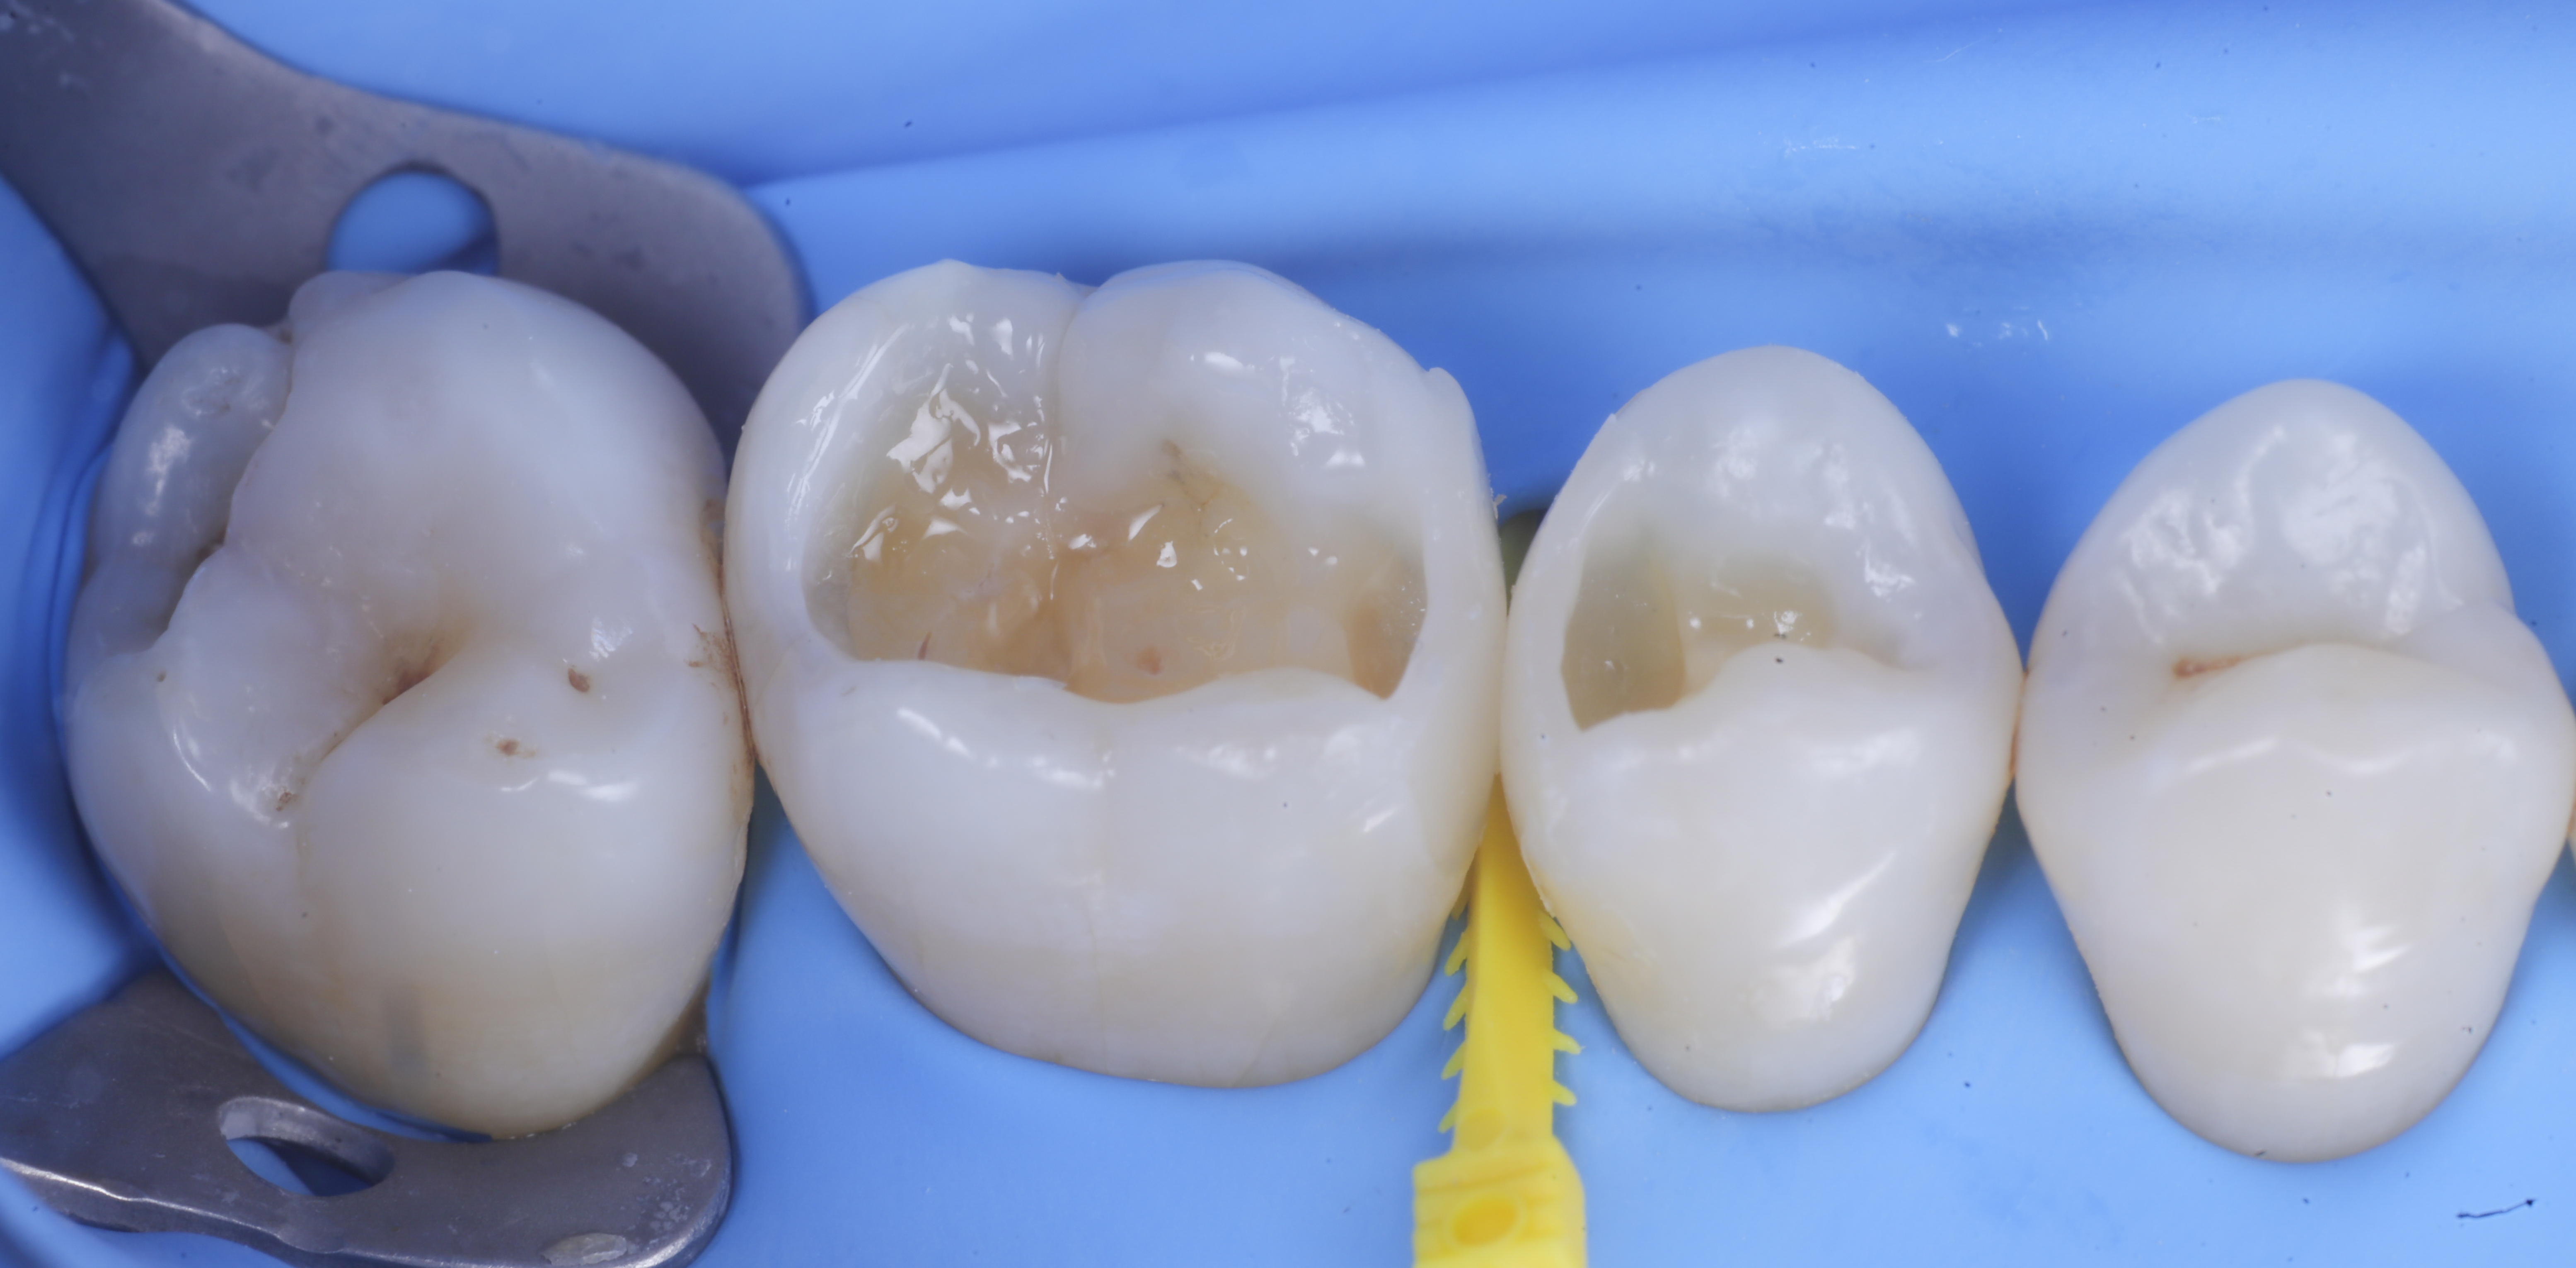

foto 1 Fotografia iniziale

foto 2 Isolamento e aspetto delle cavità ultimate